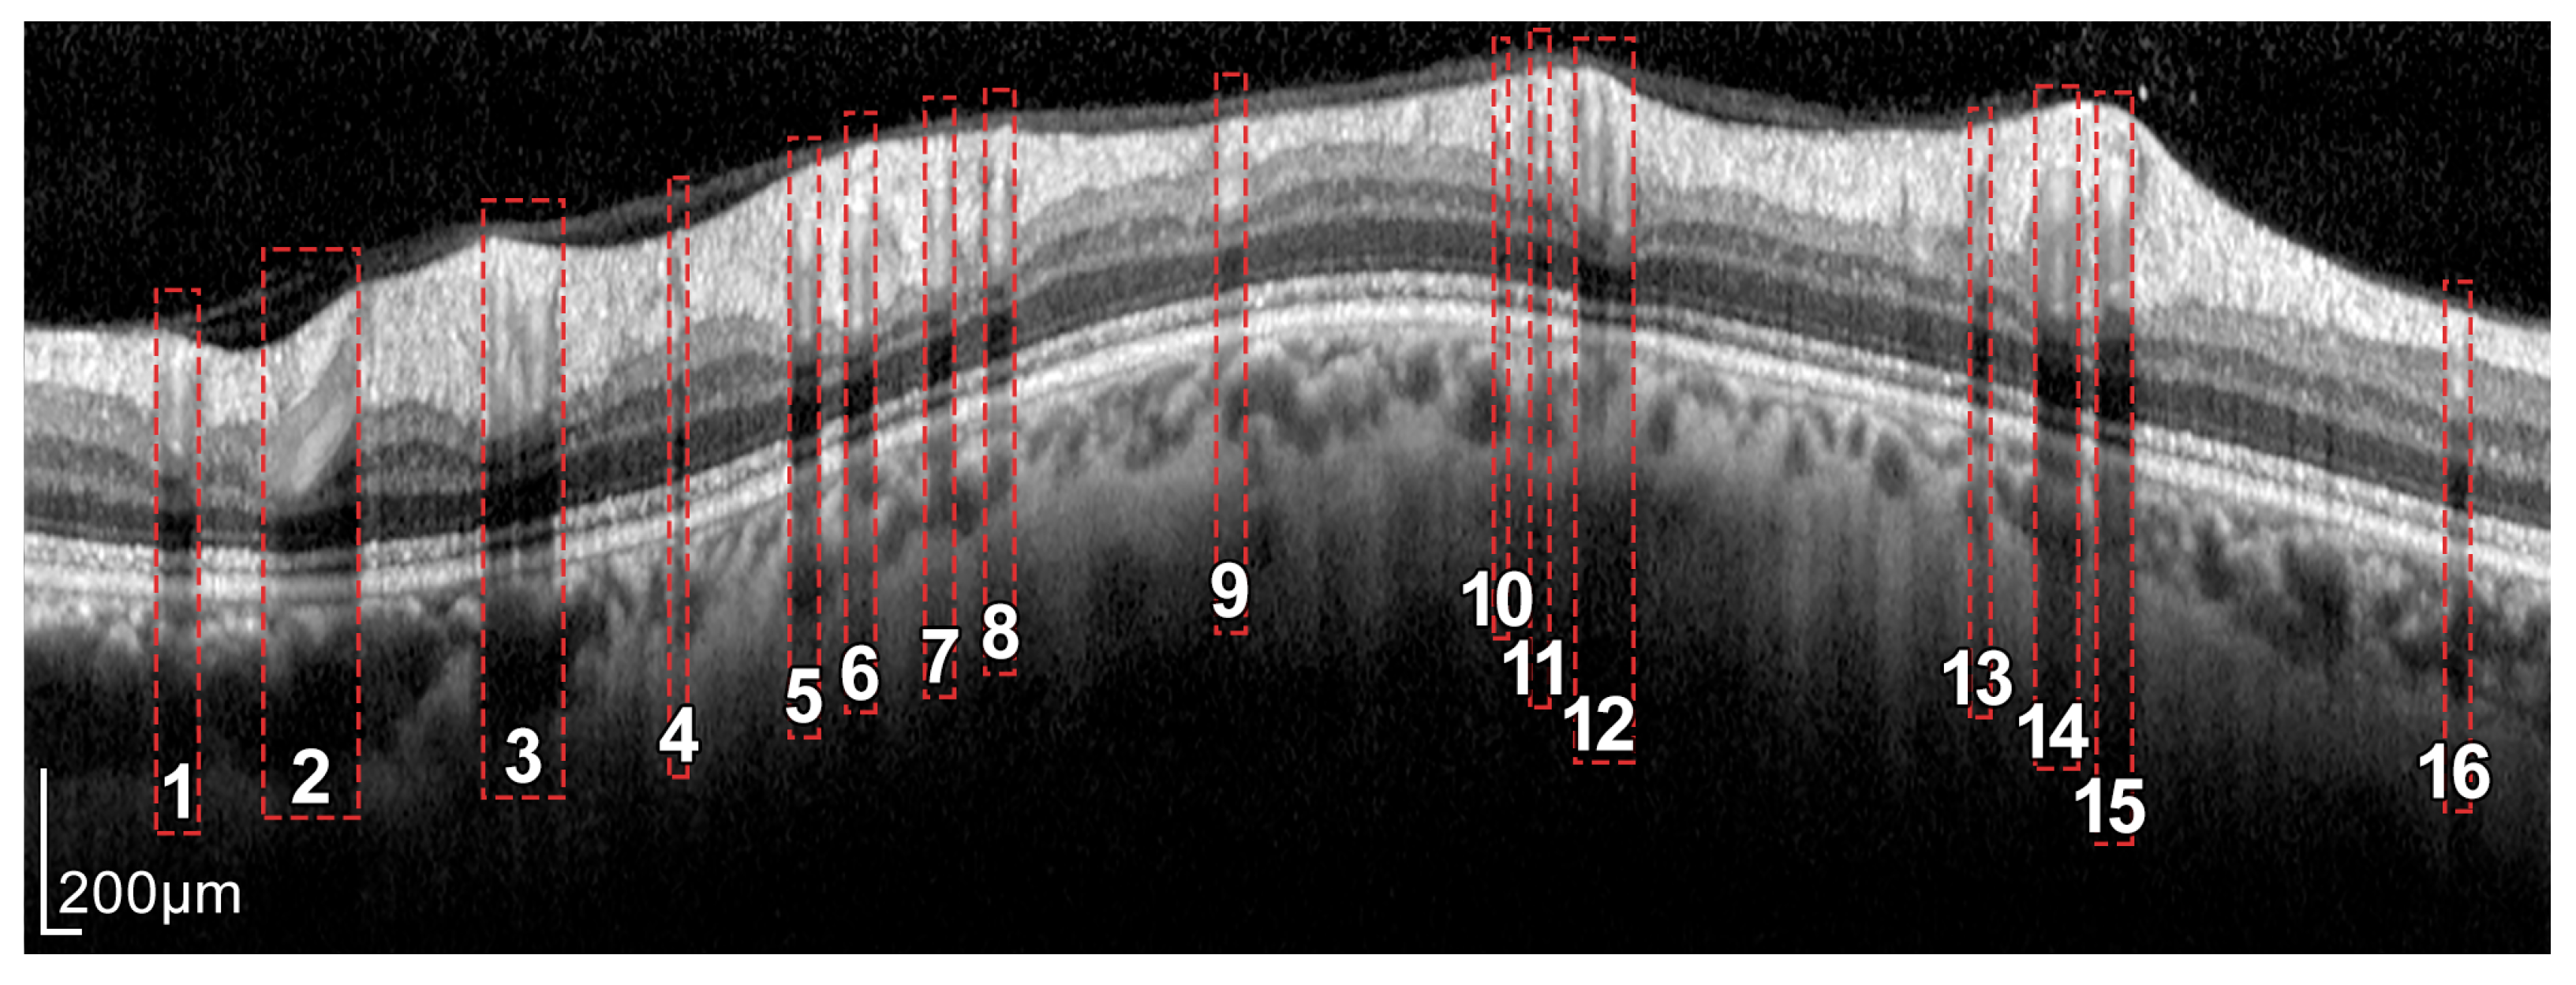

Figure 4.

Layers of the retina from top to bottom. RNFL: retinal nerve fiber layer; GCL: ganglion cell layer; IPL: inner plexiform layer; INL: inner nuclear layer; OPL: outer plexiform layer; and ONL: outer nuclear layer. Boundary delineation in the segmentation process. #1-UB: upper boundary of the RNFL; #2-AB: auxiliary boundary corresponding to the lower boundary of the ONL; #3-LB, lower boundary of the RNFL. The dashed boxes exemplify some of the artifacts of the layers.

As can be seen in Figure 3 and Figure 4, the RNFL is the innermost layer of the retina. Granular noise and various artifacts appear in the area of the image above the RNFL, which corresponds to the vitreous body. These artifacts have similar grayscale levels to the layer of interest, which leads to a more challenging segmentation process. Moreover, the transition between the RNFL and the CGL, which is located just below the RNFL, shows a low level of contrast, making the separation between these two layers a relevant issue [22].

In addition, because blood vessels are located just above the retina, a shadowing effect appears on the retinal layers. As observed in Figure 5, these vessels cross the circumference of analysis perpendicularly, casting a shadow on the retinal layers at these crossing points. This results in intensity inhomogeneities, boundary artifacts, and darkened areas in the layers to be segmented, as portrayed in Figure 6. This further complicates the segmentation of the RNFL and hence the calculation of its thickness.

The proposed approach for the segmentation of the RNFL consists of a sequential process for obtaining different layer boundaries. Figure 4 illustrates the three boundaries used in the segmentation of the RNFL layer, namely #1-UB, #2-AB, and #3-LB.